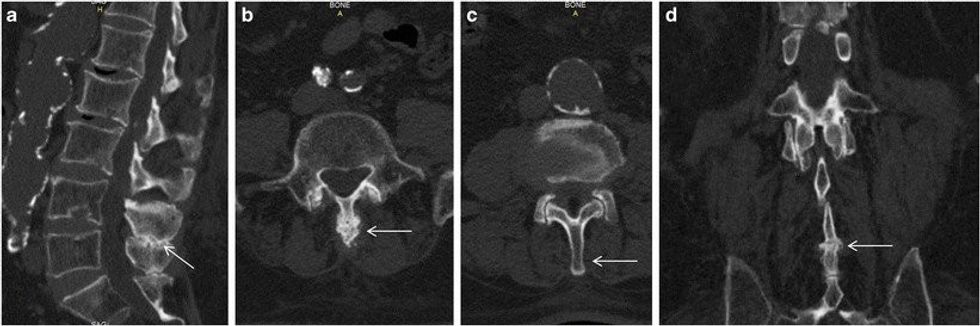

Njerëzit që kanë lordozë do të kenë më shumë hapësirë midis shtyllës kurrizore dhe sipërfaqes. Kjo lordozë mund të vërehet edhe në një pozicion në këmbë, sepse njerëzit do të kenë bark dhe të pasme të fryra, ndërsa pjesa e poshtme e shtyllës kurrizore do të jetë në formë C. Megjithatë, për t'u siguruar që është lordozë, duhet bërë një radiografi e shtyllës kurrizore.

Në disa njerëz, lordoza mund të shihet e shtrirë ose e përkulur ose duke kryer ushtrime të caktuara. Megjithatë, mënyra më e mirë për të diagnostikuar lordozën është të shkoni te mjeku ose fiziatri dhe të bëni një radiografi të shtyllës kurrizore, rezonancë magnetike ose CT.